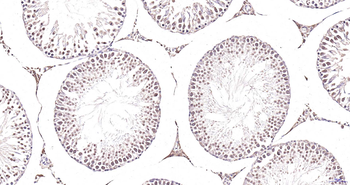

IF, IHC-Fr, IHC-P

应用稀释比例:IHC-P=1:100-500, IHC-F=1:100-500, IF=1:100-500